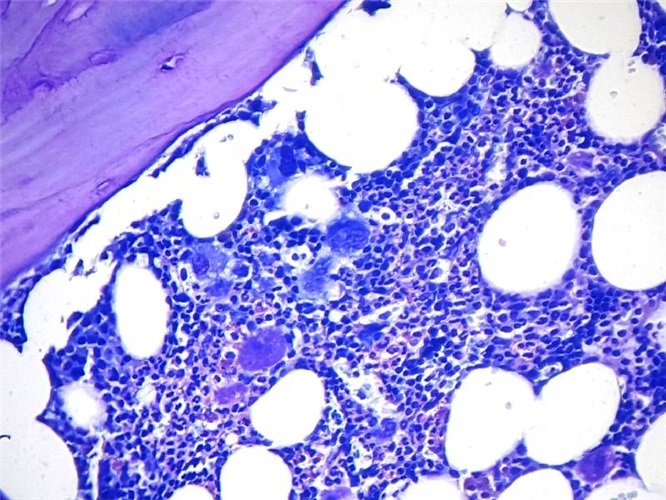

Комплект постачає реагенти для забарвлення за методом Мей Грюнвальда-Гіємси на парафінових тканинах, що підходить для типування клітин гемолімфопоетичної системи та ідентифікації паразитів.

Цей метод також можна використовувати для виявлення ендотеліального ретикулуму.